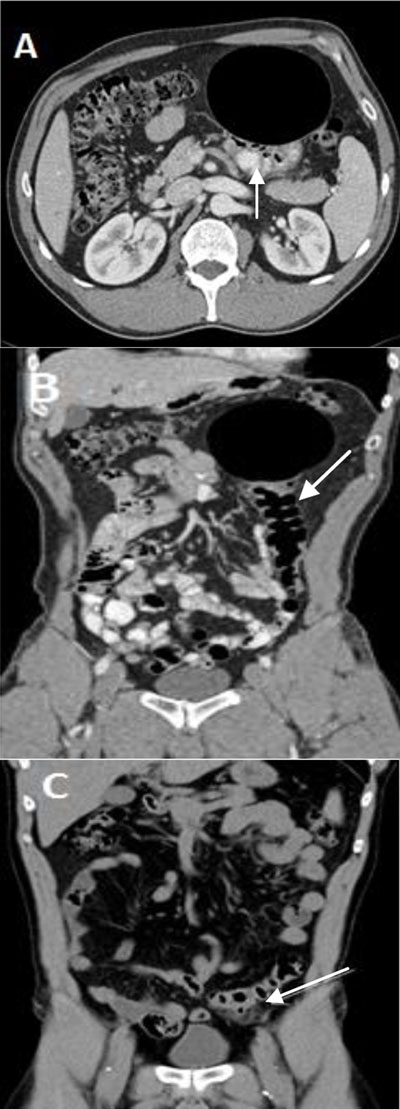

Figure 1

(A) and (B) Contrast-enhanced CT scan showing a 10.4 × 8.1 cm smooth-walled well-defined cystic air-filled lesion adjacent to the sigmoid (arrow) lifted in the left hypochondrium. (C) Unenhanced CT scan of the abdomen from one year earlier showed sigmoid diverticulitis (arrow) located in the left iliac fossa and without the cystic mass.